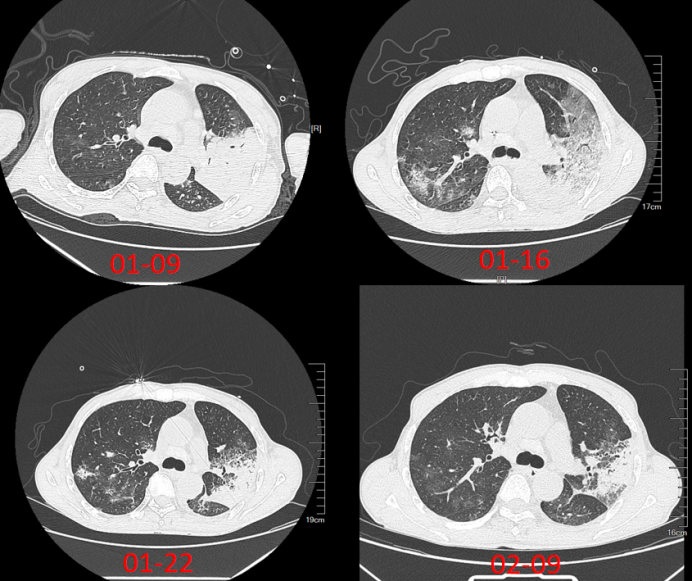

经过前述治疗,患者仍存在脏器功能障碍与炎症表现(图2-图4),床旁胸片示肺部病变快速进展,呈“白肺”样改变(图5)

图片

5  患者胸片变化情况

2025年2月8日复查胸部CT:两肺渗出较前明显进展。